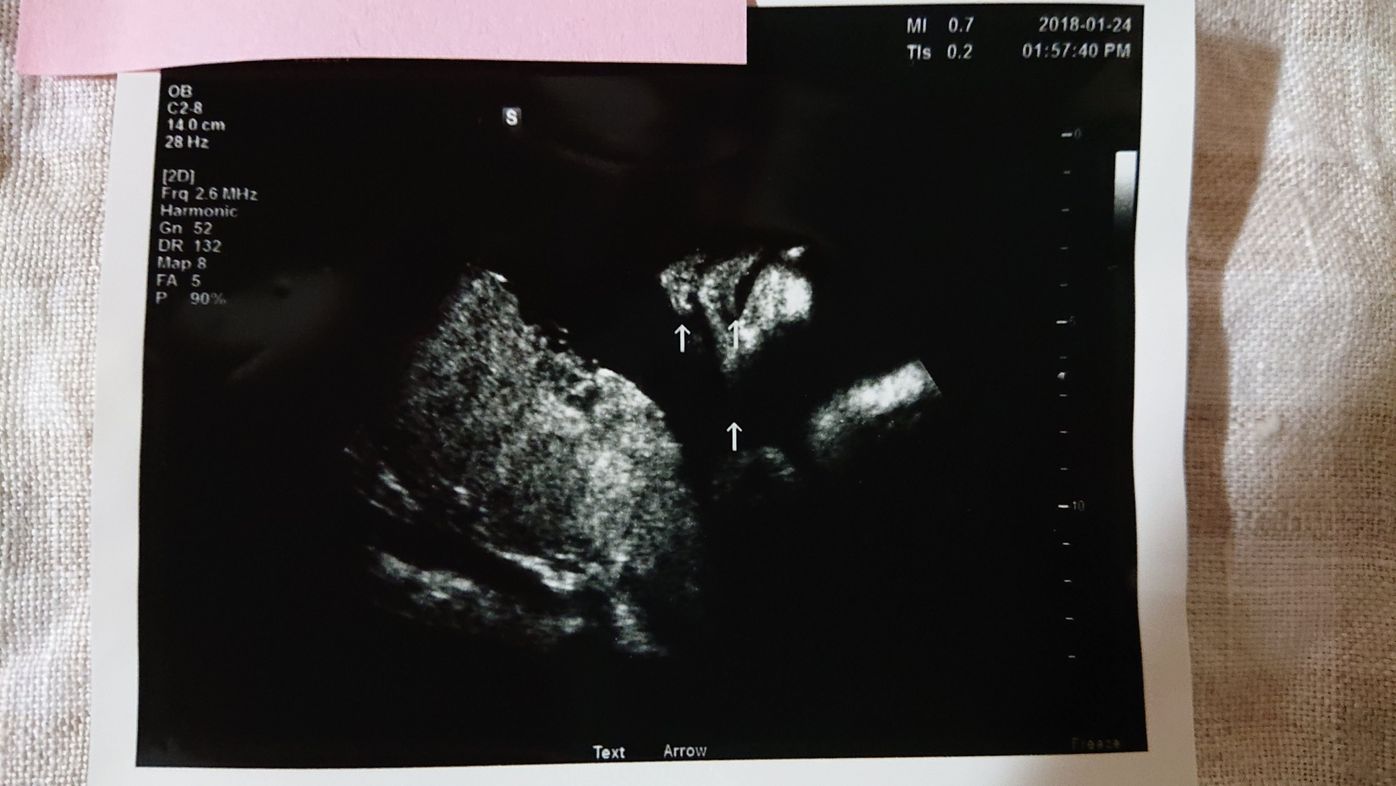

写真多数週数別女の子のエコーの見分け方!性別判定22 今日は独自に調査・お願いをして女の子のエコー写真を集めてみました! 上に足をひろげていて、よく言われるコーヒー豆のような印や葉っぱマークは見えませんが、お股のふくらみが 3人目が女の子なので最近エコーでも見てますが 葉っぱ部分はそんなに前に出ていないです💦 女の子であれば、赤く囲んだ線の左側に 葉っぱ部分が来るかな?と思いました💦 もう少し性別判定には時間がかかりそうですね。 素人の意見よりはプロの先生の

性別についてです! 先日も質問しましたが意見がちょうど半分で分かれてしまったので再度質問させてください🥲 25w4dのエコー写真です!! 男の子と女の子どちらに見えますか? 矢印の左側にお股が これぐらいの時に、エコーにきれいに写り込んでいた場合は確認ができるわけです。 しかしこれがなかなかうまく確認できないんです! ! うちの子のように、赤ちゃんの体の位置だったり、足を閉じていたりすると確認できません。 また男の子なら、はっきりとシンボルが写っている場合はほぼ断定できますが、女の子の場合はどうしても判定が難しいようです。 よく言われていたエコー写真 テーマ: マタニティ 性別判明時に「男の子だよー、これがおちんちん」ってカーソル当てて教えてくれたんだけどイマイチわからず。 「はぁ、これがそうなんですかぁぁ」と答えつつ、帰宅したら不安になってきた。 私の